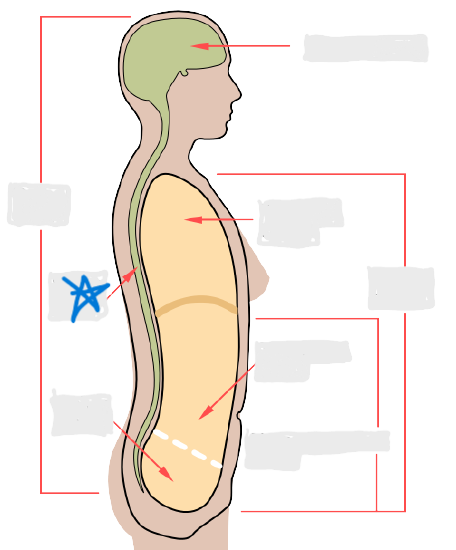

axial

cephalic

occipital

frontal

otic

orbital

nasal

oral

mental

cervical

dorsal

scapular

vertebral

lumbar

sacral

gluteal

thoracic

sternal

mammary

axillary

abdominal

umbilical

pelvic

inguinal

pubic

perineal

appendicular

acromial

brachial

antecubital

olecranal

antebrachial

carpal

manus

coxal

femoral

patellar

popliteal

crural

sural

peroneal

calcaneal

plantar

cranial cavity

vertebral cavity

pleural cavity

pericardial cavity

mediastinum

abdominal cavity

pelvic cavity